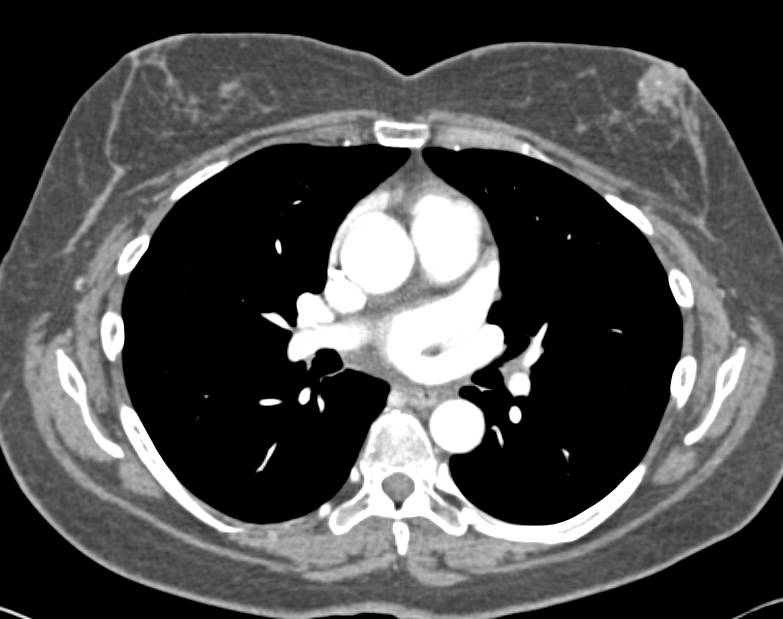

Takayasu's Arteritis Involves Left Subclavian Artery and Arch